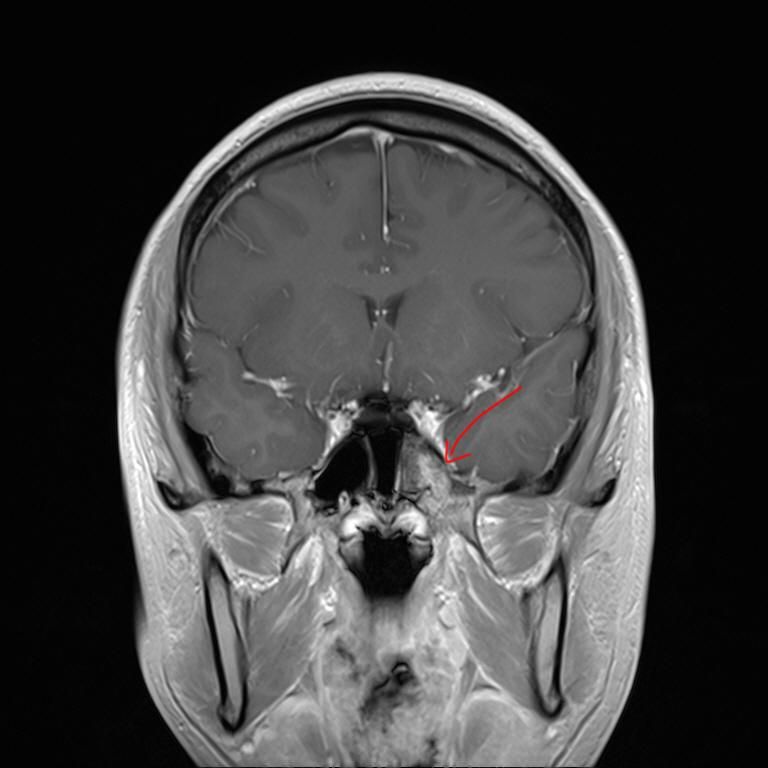

mri 사진을 봤을 때 정확히 어디가 막힌 걸까요? 그리고 치료는 할 수 있는 걸까요???

• 3번 째 사진

올려주신 영상 관련 보다 더 자세한 분석 원하시면 영상의학과 전문의한테 물어보셔야 해요

말씀하신 증상 관련 답변 드리자면 15년동안 지속된 귀와 코 사이 막힘 증상은 이관(유스타키오관) 기능 장애일 가능성이 높습니다. 진한 콧물을 강하게 들이마신 후부터 증상이 생겼다면, 이관이 분비물이나 압력 변화로 막히거나 손상되었을 가능성이 있습니다. 이관은 코 뒤쪽과 귀 중이를 연결하는 통로로, 막히면 귀먹먹함, 압력감, 울림 증상 등이 지속될 수 있습니다. MRI나 CT를 통해 이관 주변 구조(비인두, 부비동, 중이강 등)의 해부학적 이상을 더 정확히 확인해야 합니다.